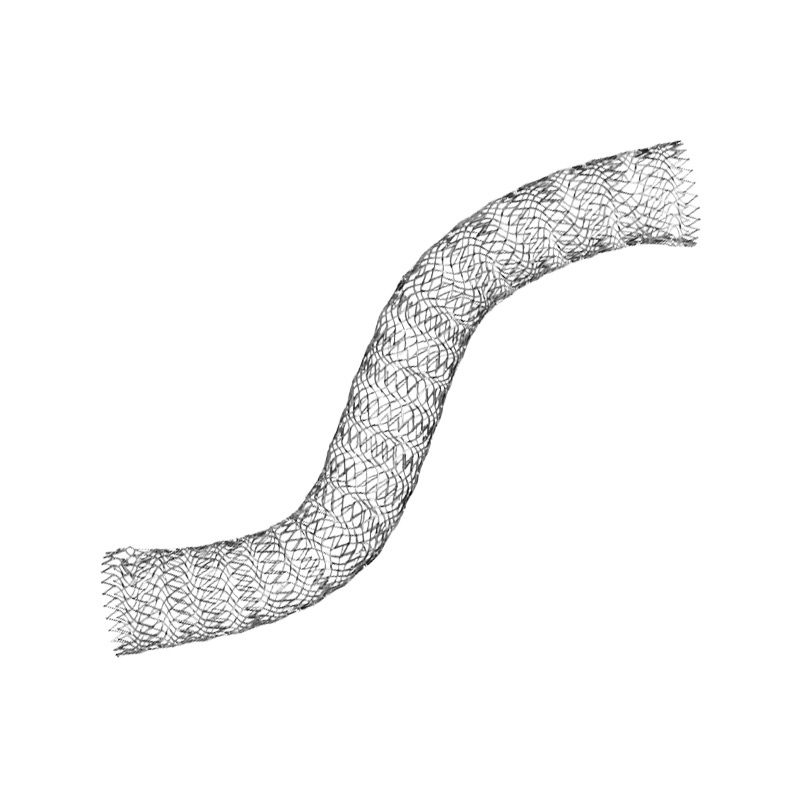

Interventional treatment of venous thrombosis

from acute DVT to post-thrombotic lesions